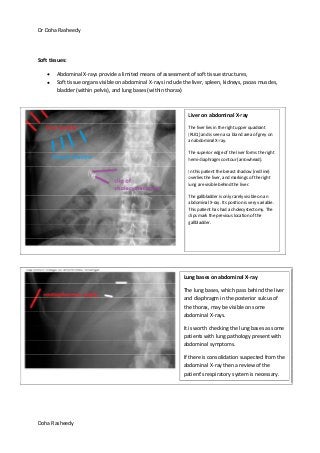

Soft tissues:

Abdominal X-rays provide a limited means of assessment of soft tissue structures,

Soft tissue organs visible on abdominal X-rays include the liver, spleen, kidneys, psoas muscles,

bladder (within pelvis), and lung bases (within thorax)

Liver on abdominal X-ray

The liver lies in the right upper quadrant

(RUQ) and is seen as a bland area of grey on

an abdominal X-ray.

The superior edge of the liver forms the right

hemi-diaphragm contour (arrowhead).

In this patient the breast shadow (red line)

overlies the liver, and markings of the right

lung are visible behind the liver.

The gallbladder is only rarely visible on an

abdominal X-ray. Its position is very variable.

This patient has had a cholecystectomy. The

clips mark the previous location of the

gallbladder.

Lung bases on abdominal X-ray

The lung bases, which pass behind the liver

and diaphragm in the posterior sulcus of

the thorax, may be visible on some

abdominal X-rays.

It is worth checking the lung bases as some

patients with lung pathology present with

abdominal symptoms.

If there is consolidation suspected from the

abdominal X-ray then a review of the

patient's respiratory system is necessary.